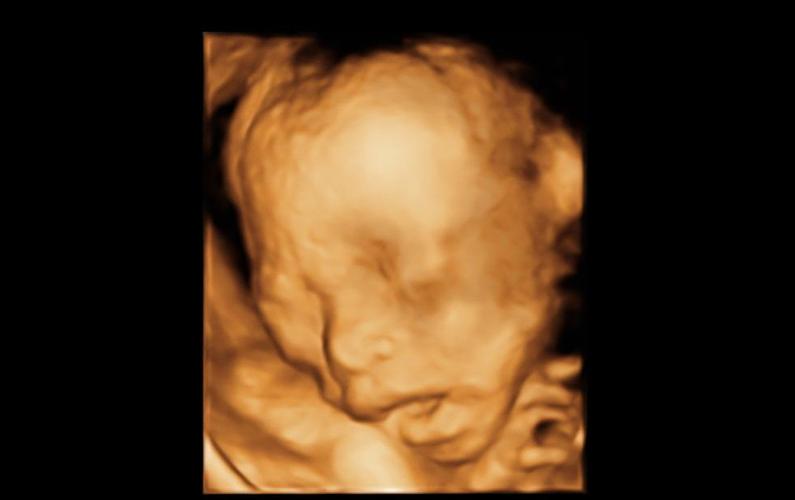

在怀孕第13周后,B超可以清晰显现胎儿的头颅、躯干、心、肺、肝、脾、胃、肾、膀肤等器官和四肢骨骼的情况。通过测量所得的数据,可估计胎儿发育情况,还能确定胎位及胎盘位置,评价胎盘功能,选择分娩方式。

(1)第1次在怀孕18^-20周。此时可以确定是单胎还是多胎,并可测量胎儿的头围等。

(2)第2次在怀孕28---30周。此时是了解胎儿发育情况,是否有体表畸形。

(3)最后1次在怀孕37-40周。此时确定胎位、胎儿大小、胎盘成熟程度、有无脐带绕颈等,进行临产最后评估。